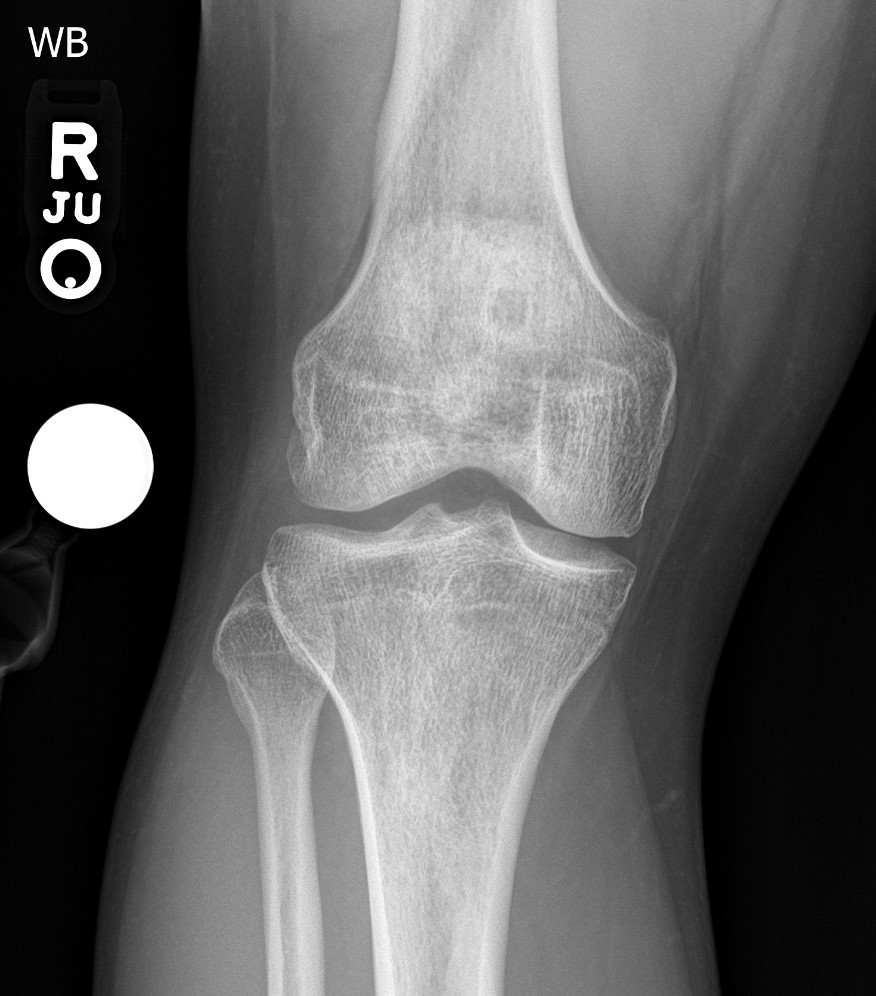

gout arthritis ( rid3567 )